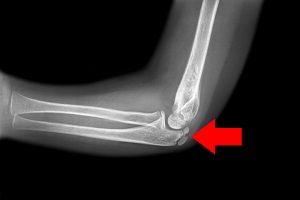

Radial Head Fracture

Radial head fractures are very common and occur in almost 20% of acute elbow injuries. Elbow dislocations are generally associated with...